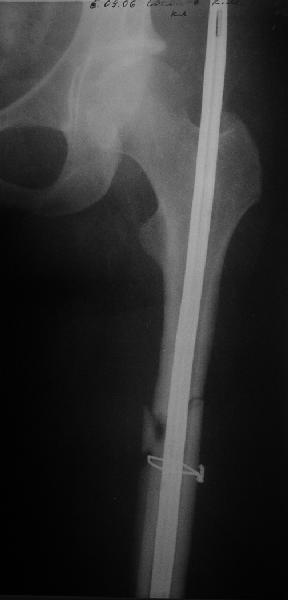

Несращение бедра

Пациент попал под наше наблюдение через 3 недели после первого остеосинтеза (фото 1). Учитывая, нестабильность остеосинтеза, выстоящий стержень закрыто перештифтовали (фото 2), через 3 месяца динамизация. К 5 месяцам имели укорочение 2 см, при том, что динамический винт стал статическим. От дальнейшей динамизации отказались, учитывая наличие контакта между фрагментами и возможность прогрессирования укорочения. К 1,5 года сращение не достигнуто (фото 3). Удалили гвоздь, выполнили дистракционный остеосинтез с целью стимуляции остеогенеза и компенсации укорочения (фото 4), потом закрыто перештифтовали после рассверливания (фото 5). На сегодняшний день, через 4 месяца после последней операции (фото 6) признаков регенерата нет, длина восстановлена, ходит без дополнительной опоры.

Возможные варианты: 1)подождать - однако регенерата не заметно 2)Снова потерять длину (динамизация, компрессирющий остеосинтез на этом гвозде, после перепроведения проксимальных винтов и копрессирующей заглушки, восстановление длины после сращения) 3)Костная пластика